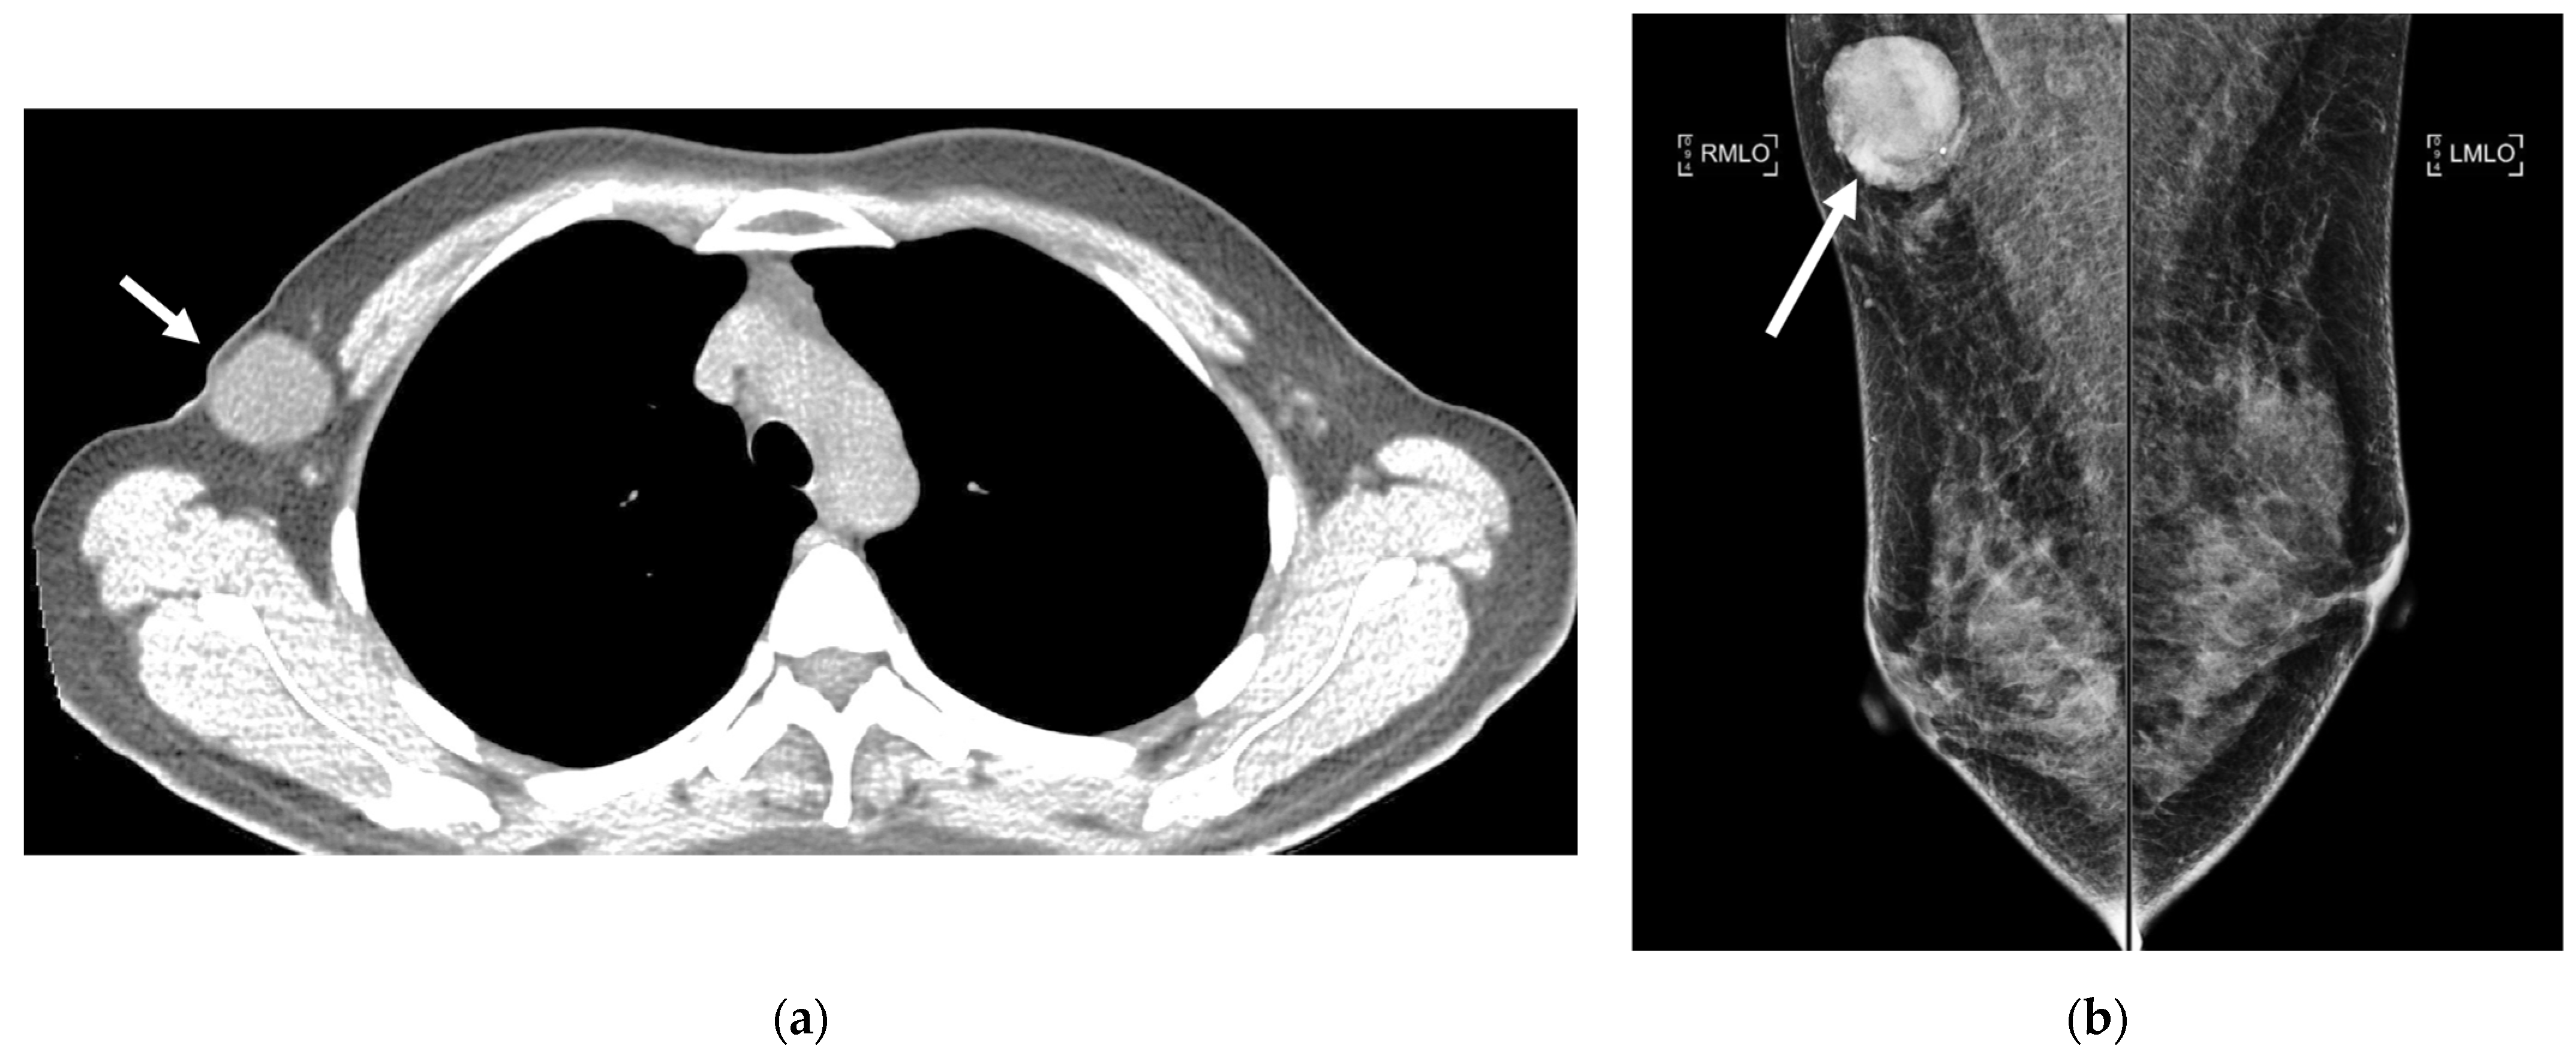

5.3.1. Liver